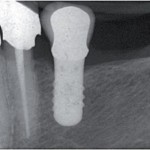

Ricostruzioni platform-switched su impianti di largo diametro: uno studio clinico prospettico di cinque anni

Platform-switched restorations on wide-diameter implants: a five-year clinical prospective study

Vigolo P,...